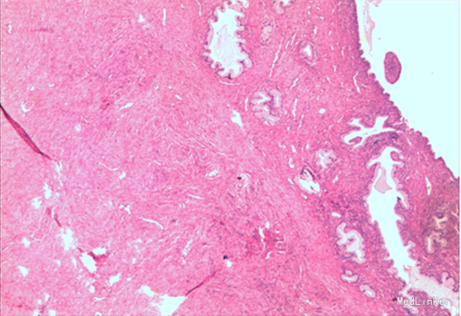

诊断:子宫脱垂III度、阴道前壁中度膨出、阴道后壁轻度膨出 手术方式:阴式全子宫切除术+阴道前后壁修补术